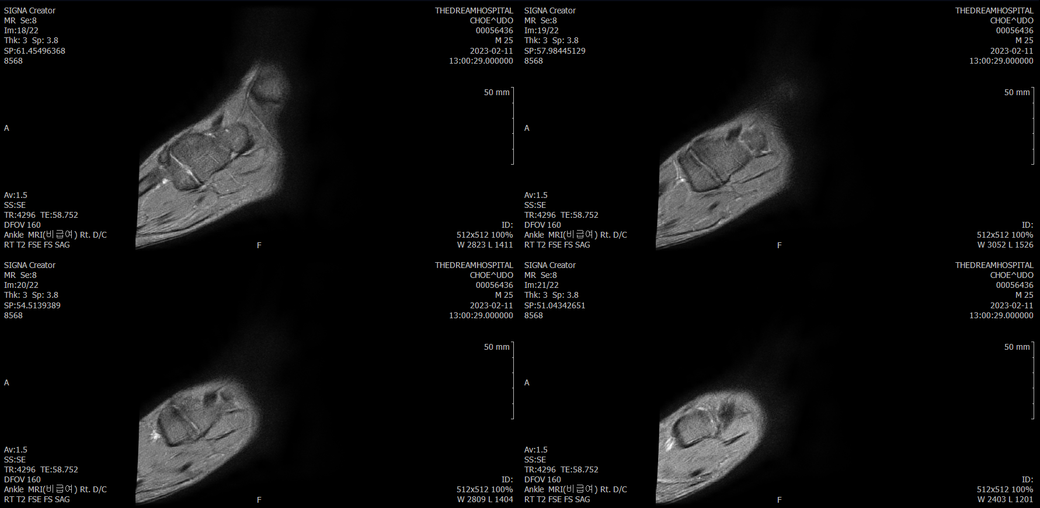

오른발목 mri 전체사진입니다. 제가 병원을 갈수없는상황인지라.... 봐주시면 감사하겠습니다.

엑스레이에서는 문제가 없다고 하여 오른발목 mri촬영했습니다.

우선 전반적으로 봤을 때 큰 이상은 없어보입니다.

전거비인대 등도 저명한 손상은 없는 것 같아 보이지만, 어느 부분의 통증 등으로 인해 촬영을 하셨는지 말씀을 해주신다면 보다 정확한 병변파악이 가능하겠으며, 병원에서 판독이 완료되신다면 전화 등으로 문의를 해보시는 것이 좋겠습니다.